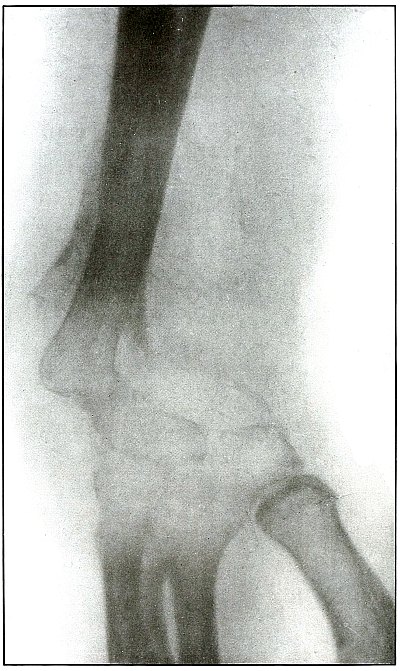

[Pg 96]

Plate 43.

[Pg 97]

Rifle—Plate 43.

UPPER EXTREMITY.

Gunshot Fracture of the Metacarpus.

Wound of entrance, inner aspect of the hand over proximal end of the

fifth metacarpal.

Wound of exit, on the outer border of the hand over the distal end of

the second metacarpal.

The velocity of the bullet was in mid or long range, as it displaced

no fragments, and as it made a point of entrance and exit about the

same in appearance.

The wound was infected, which is more frequently the case in the hand

than in the forearm.

The treatment is conservative with free incision and drainage

in the management of infection.